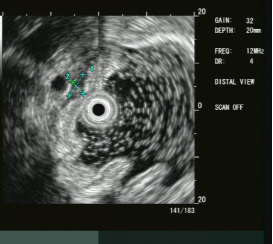

大型超声内镜下(EUS)胰腺占位性病变的FNA/FNB技术

内镜超声小探头行胃、肠道粘膜下隆起病变诊断